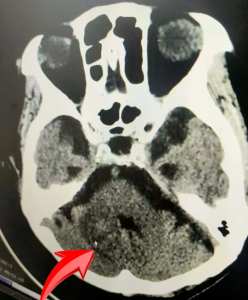

图二:出血病灶已基本吸收

一周后,患者生命体征神志逐渐平稳,复查头颅CT未发现有继续出血征象,而且出血病灶较前稍有减少,大家悬着的一颗心终于放下来。

经过近一个月的有效治疗,在全科医护的共同努力之下,该患者神志清醒,肢体自主运动有所恢复,肺部感染明显好转,近日复查头颅CT,出血病灶已基本吸收,目前该患者病情好转出院。